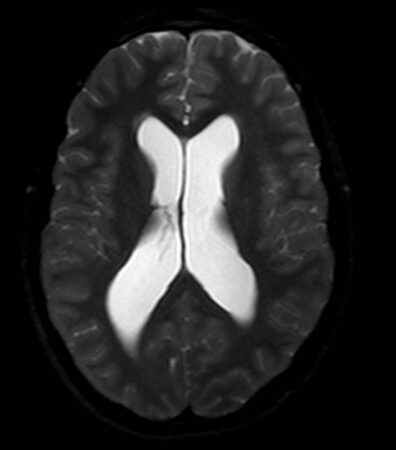

Shown are two different views of an MRI scan of Braden Parson’s brain that revealed he had hydrocephalus. The white area shows the brain’s ventricles, which in Braden’s case were enlarged with too much cerebrospinal fluid. The fluid compresses the brain tissue inside the skull.